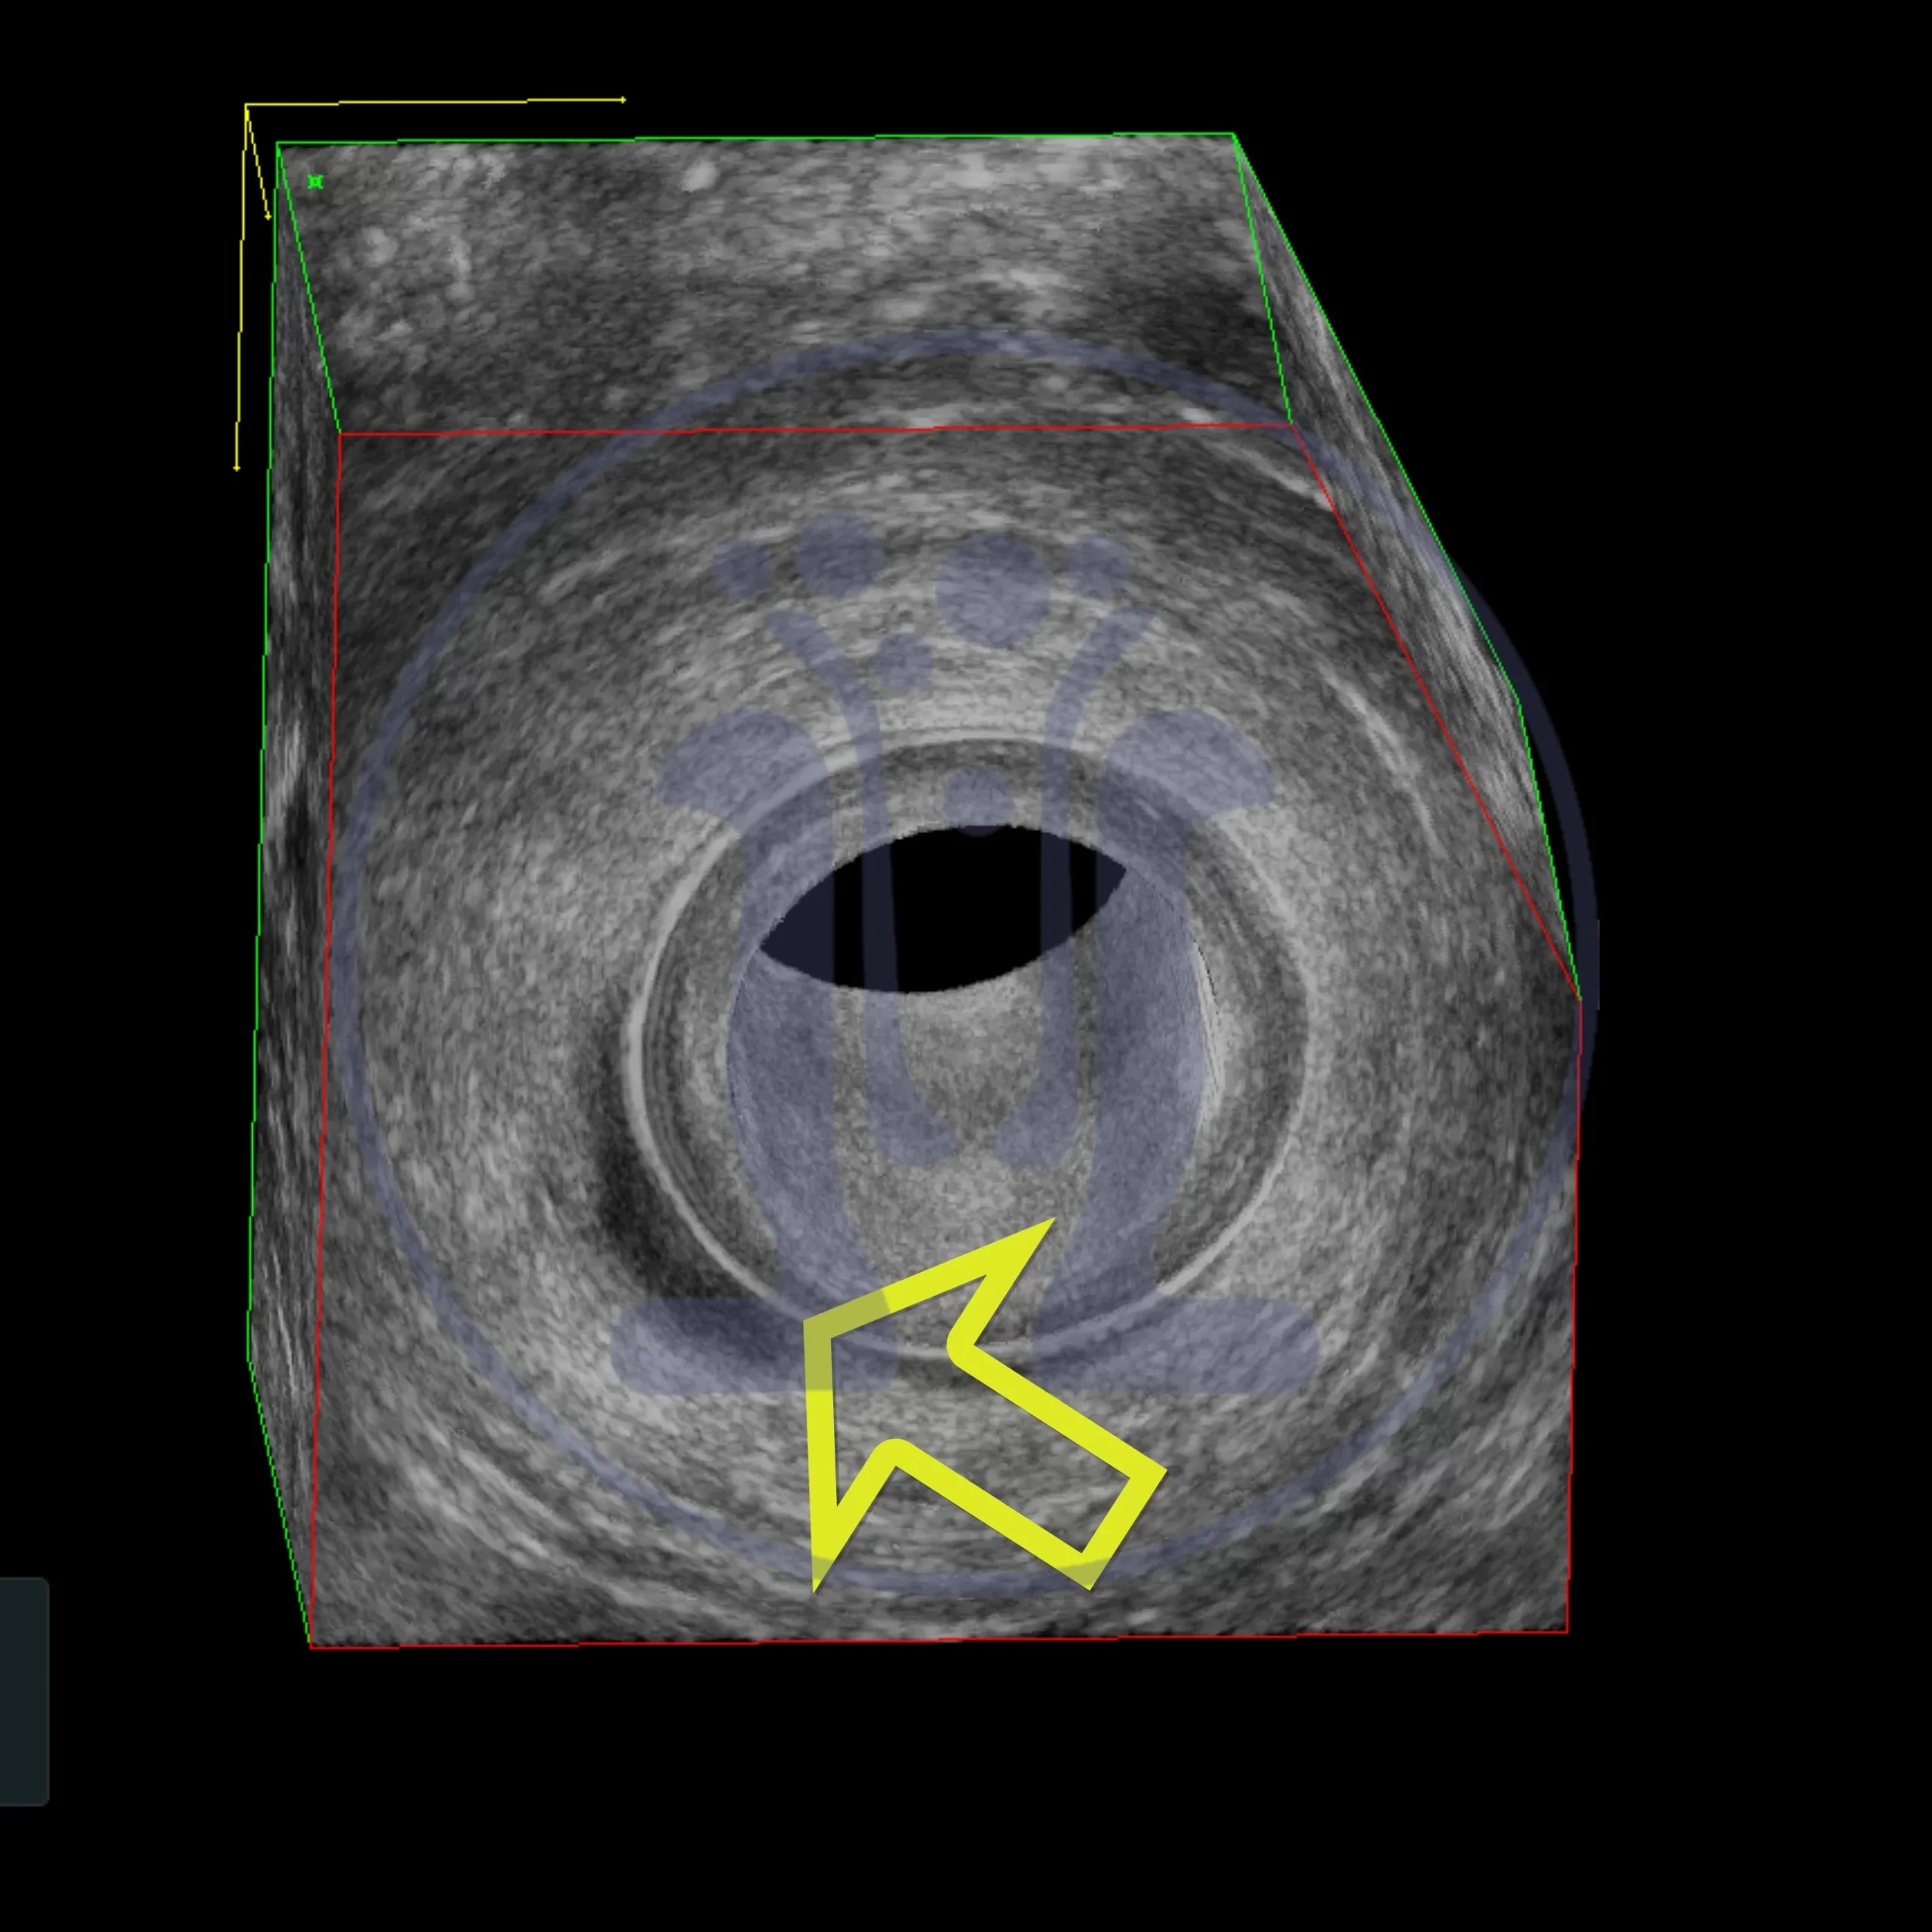

Αυτή την εβδομάδα συναντήσαμε το πέμπτο περιστατικά της διετίας με έντονο πόνο στον πρωκτό που προκλήθηκε από φυτικούς σπόρους. Αυτή την φορά ο ένοχος ήταν ο λιναρόσπορος…Αφαιρέθηκε ο λιναρόσπορος αλλά τελικά χρειάσθηκε επιπλέον χειρουργικός καθαρισμός..